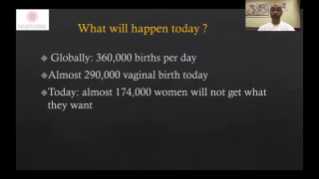

System Nuewa zosta? stworzony specjalnie na potrzeby zdrowia kobiet w okresie przed ci???, w trakcie ci??y i po?ogu. Oparty na zaawansowanej platformie ZST+ oferuje pe?n? gam? inteligentnych rozwi?zań i pozwala na wszechstronn? oraz efektywn? diagnostyk?, wspieraj?c codzienne wyzwania kliniczne.